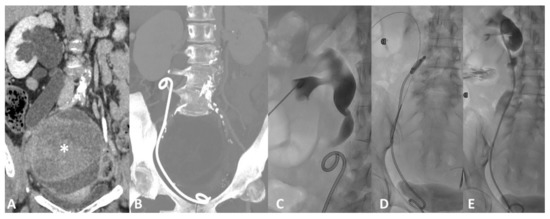

4.3. Obstruction

4.4. Perforation